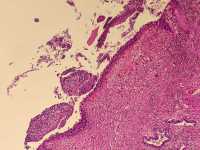

女39岁宫颈活检HPV53HPV58阳性 CIN2?

免疫组化分别是P16 Ki67

考虑为CIN2累腺

HSIL累腺。